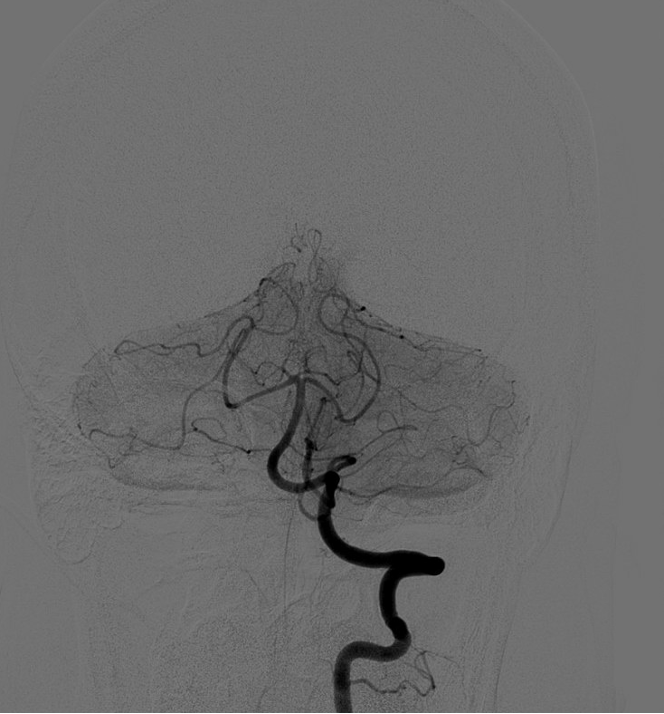

Pathologic early filling of this structure is seen on this AP view of the R CCA injection:

Cavernous sinus